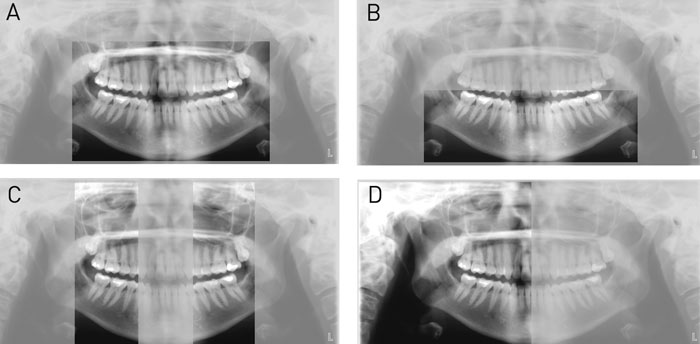

Med mange moderne panoramaapparater kan den effektive dosis reduceres ved vertikal og horisontal indblænding af det standardmæssigt bestrålede område, således at kun det absolut relevante område eksponeres. Indblænding kan fx resultere i billedgengivelse af kun den tandbærende del af kæberne, over- eller underkæben alene, kæbernes molarområder alene, højre og/eller venstre kæbeledsregion alene, osv. (Fig. 11A-D). Indblænding medfører stor reduktion i den effektive stråledosis og kan desuden resultere i mere effektiv billedtolkning, da tandlægen så kun skal forholde sig til et mindre og mere specifikt udsnit af patienten.

Fig. 11 A: Panoramaudsnit af den tandbærende del af kæberne. B: Panoramaudsnit kun af underkæbe. C: Panoramaudsnit af over- og underkæbens molarområder. D: Panoramaudsnit kun af patientens højre side.